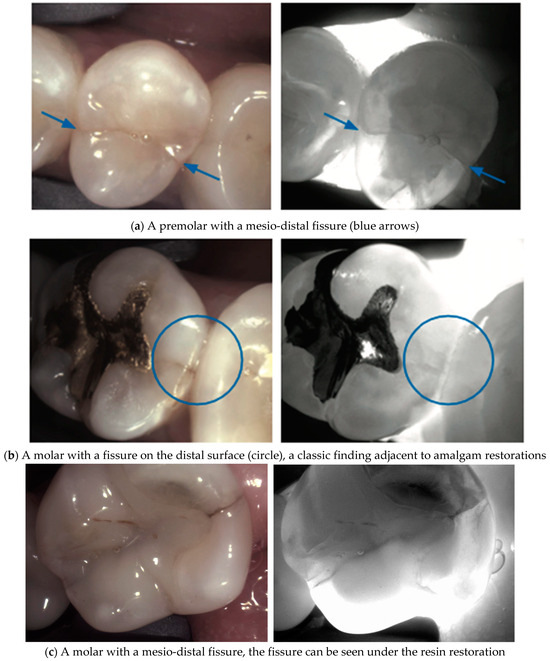

4. Enamel Defects